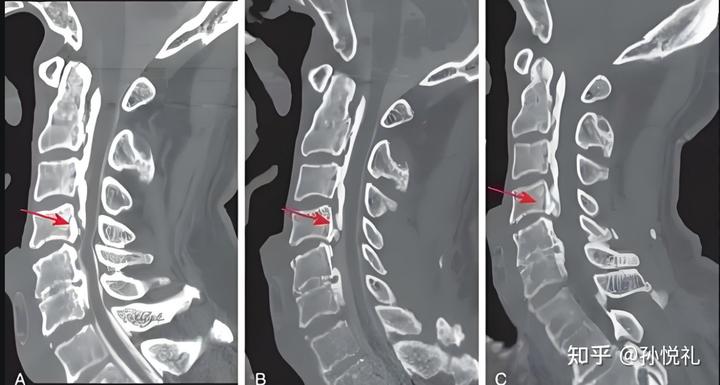

在骨科临床中,我们经常见到一些“先天少长了一点骨头”的人,比如某些肋骨缺如、副骨缺失,甚至髌骨发育异常。很多这类患者一辈子都活得很好,甚至直到拍片时才第一次发现自己的解剖结构和别人不完全一样。原因就在于,那些缺失的结构并不处在人体力学的关键链路上,它们既不承担主要负重,也不维持关节稳定,更不保护重要神经。